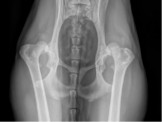

Lire la suiteLes vétérinaires invités à participer à un projet de recherche sur la dysplasie coxo fémorale chez le chien

L’équipe “ Génétique du chien ” (CNRS-Rennes 1) poursuit ses recherches sur lla dysplasie coxo-fémorale. Les vétérinaires sont invités à participer à ce travail.